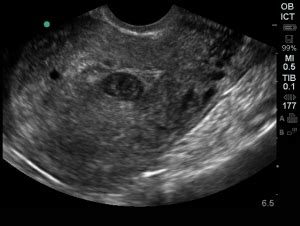

So, how do the docs actually figure out if what they’re seeing on the ultrasound is a pseudogestational sac or the real deal? It’s all about careful observation and looking for specific clues, guys. The primary tool here is, you guessed it, an ultrasound . Early in pregnancy, a true gestational sac typically has a very specific appearance. It’s usually a well-defined, round or oval structure within the uterine lining, often described as having a ‘double-decidual sac sign’. This sign refers to the interface between the decidua capsularis and the decidua parietalis, creating a distinct ring around the developing sac. A pseudogestational sac, on the other hand, often looks less defined. It might be eccentrically located within the uterine cavity and often lacks that clear double-decidual sac sign. It can appear more like a ‘sludge’ or a collection of fluid within the thickened uterine lining, rather than a distinct, well-formed sac. Transvaginal ultrasound is usually preferred for these early assessments because it provides a much clearer and more detailed image of the uterus and surrounding structures compared to a transabdominal scan. What else are the doctors looking for? They’re searching for other definitive signs of an intrauterine pregnancy. This includes the presence of a yolk sac , which is one of the first visible structures within the gestational sac, and later, a fetal pole or embryonic heartbeat . If an ultrasound shows a decidualized uterine lining and a sac-like structure, but no yolk sac or embryo is seen, especially after a certain gestational age (often around 5-6 weeks of pregnancy), the suspicion for a pseudogestational sac increases significantly. Serial ultrasounds are often employed. This means repeating the ultrasound a few days or a week later. If it was a true early pregnancy, you’d expect to see growth – the yolk sac developing, the sac enlarging, and maybe even a heartbeat. If the ‘sac’ remains unchanged or the decidual reaction simply resolves, it further supports the diagnosis of a pseudogestational sac, indicating a non-viable pregnancy or no pregnancy at all. Beta-hCG levels (the pregnancy hormone) also play a crucial role. In a normal intrauterine pregnancy, hCG levels rise predictably. In cases of ectopic pregnancy or non-viable intrauterine pregnancy, hCG levels might rise slower, plateau, or even fall. Comparing the ultrasound findings with the trend of hCG levels helps clinicians make a more accurate diagnosis. So, it’s a combination of what the ultrasound shows, the absence of key pregnancy markers, and the pattern of hormone levels that helps doctors differentiate a pseudogestational sac from a healthy, developing pregnancy. It’s a puzzle, and they’re looking for all the pieces.